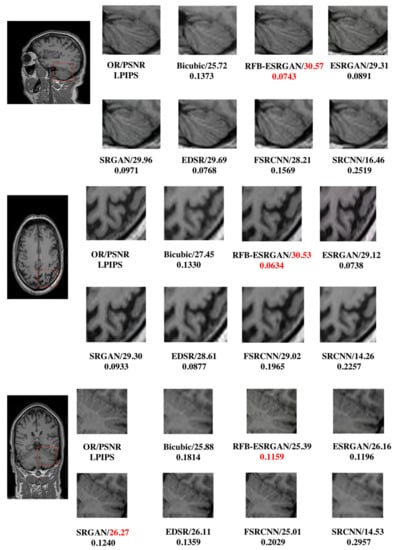

4.2. MRI Reconstruction Comparison

After using RFB-ESRGAN for the first reconstruction, we performed the second MRI reconstruction. The recombined MRI image was very noisy and had missing values. Our previous work involved repairing images according to the principle of linear interpolation, using effective pixel value interpolation instead of null values to obtain a new high-resolution MRI image. Nevertheless, our method still has a small amount of noise, and the visual effect is average [37]. Therefore, we compared our proposed nESRGAN with the previous work. After reconstruction, we tested three slices under three planes. As shown in Figure 12, the performance of nESRGAN was far better than our previous work [38]. At the same time, we also compared nESRGAN with advanced super-resolution methods. The MRI image reconstructed by SRCNN had a different brightness between adjacent slices and insufficient detail information. EDSR recovered some detailed information, but there was still noise. Overall, nESRGAN performs better than other methods in visual quality and image evaluation (Figure 12). Based on nESRGAN, we reconstructed the image after the first rebuilding. We realized super-resolution reconstruction of MRI images on the two-dimensional level through the two networks’ reconstruction work, successfully replacing the three-dimensional convolutional neural network.

Figure 12.

Comparison of bicubic, interpolation [38], advanced methods, and nESRGAN. Among them, (a) is the original high-resolution MRI slice, (e) is the slice from reconstructed MRI in the first reconstruction. (b,f) are new slices after interpolation repair. Besides, (d,g,h) are advanced super-resolution methods in deep learning. (c) is our proposed method nESRGAN(nosed-based enhanced super-resolution generative adversarial network). (b,d,f,h) still exits a few noises and grid lines which missing value lead. (c,g) perform better than others. The performance of visual quality between (c) and (d) is similar. Furthermore, (c) performs better than (d) in the image quality evaluation.